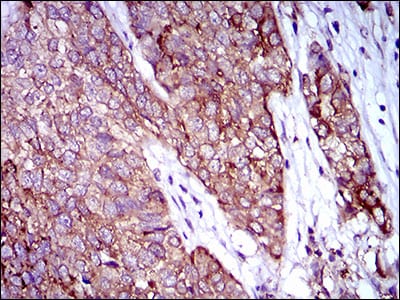

- Immunohistochemical analysis of paraffin-embedded human lung cancer tissues using ZFP42 mouse mAb with DAB staining.

- Immunohistochemical analysis of paraffin-embedded human bladder cancer tissues using ZFP42 mouse mAb with DAB staining.